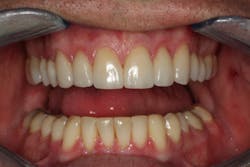

Following the orthodontics, we prepared the maxillary arch for indirect restorations and placed Darren in temporary restorations. We also restored the mandibular incisal edges with direct composites to seal any exposed dentin and refine the incisal plane using a thermoplastic stent fabricated from our diagnostic wax-up. Utilizing a stent to place the direct composites on the incisal edges saved time, and we were able to obtain greater precision in the incisal edge position. Darren was then sent to the periodontist to have the gingival architecture corrected.

Darren remained in the provisionals for three months to allow the soft tissue to fully heal. This also allowed us to evaluate the esthetics, phonetics, occlusion, and function. The importance of provisional restorations cannot be understated, as they provide us with a trial before we place the definitive restorations.

The provisionals were especially important in this case as we had to work out the anterior guidance to be in harmony with the patient's envelope of function. When the provisional restorations were initially placed, Darren continued to feel “locked in” with the position and contours of his canines. Over several appointments, we had to slightly adjust his guidance until he was comfortable while still retaining the function and esthetics.